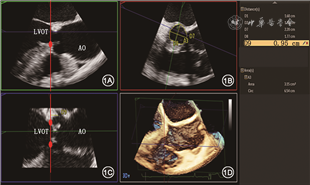

主动脉瓣环径的测量结果是TAVR人工瓣膜型号选择的依据,目前绝大多数中心主要依赖CT测量结果进行判断,但在某些特殊情况下,如急诊TAVR未行CT检查、CT图像质量不佳、对造影剂过敏或者肾功能不全的患者,则主要根据超声测值进行选择。既往研究发现主动脉瓣环呈椭圆形,因此3D超声测量比2D更准确。3D TEE与CT测量的主动脉瓣环面积和周长具有高度的一致性,可作为CT的替代检查[8]。常规3D TEE测量主动脉瓣环径的方法和CT类似,在获得主动脉根部三维容积后,使用三维分析软件获得主动脉根部矢状位、冠状位以及横断面,在矢状位及冠状位切面确定三个瓣叶附着最低点,此三点即构成主动脉瓣环横切面,在该平面进行主动脉瓣环最大径、最小径、周长及面积的测量(图1)。目前也有专门针对主动脉瓣环测量的三维半定量分析软件,可以自动计算主动脉瓣环相关径线,与CT测值间相关性较好[9, 10]。

LVOT为左心室流出道,AO为主动脉

主动脉根部径线测量还包括左心室流出道(LVOT)内径、主动脉窦部内径和高度、窦管交界处内径、升主动脉内径以及冠状动脉开口距主动脉瓣环的距离(简称冠脉高度),这些测值均会影响TAVR人工瓣膜型号的选择和瓣膜置入的策略。主要径线的测量方法如图2。冠脉高度建议应用3D TEE测量更准确,确定瓣环水平后,调整主动脉根部矢状位和冠状位切线,分别通过右冠状动脉和左冠状动脉开口,分别在矢状位和冠状位测量右、左冠状动脉开口高度(图1)。